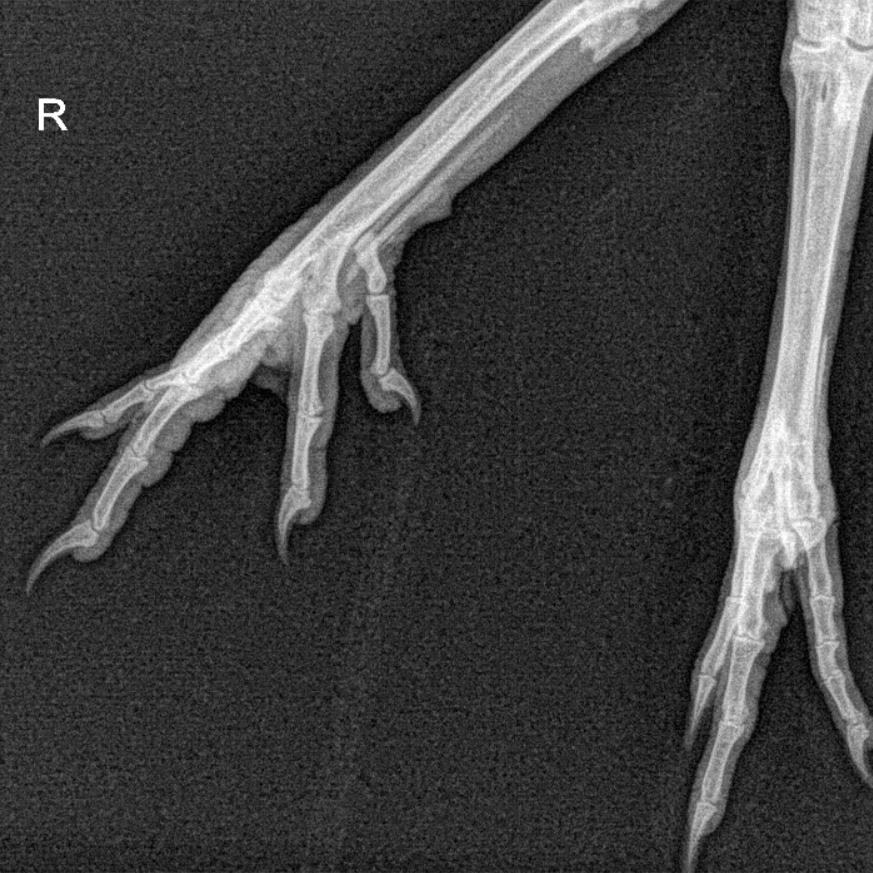

Once Dr. Strickland reviewed the radiographs, he informed Kelly that Checkers had a non-displaced fracture of the middle digit on the first phalange in his right foot. He also showed Kelly the radiograph and pointed out exactly where the fracture was located. Dr. Strickland explained how that since it was a minor fracture, Checkers would be okay without a splint or bandage and that the lesion would likely heal in 2-3 weeks.

Radiograph of Checker’s fracture